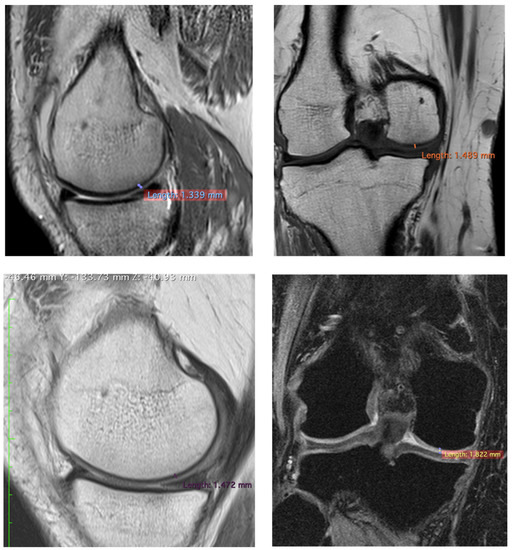

| Patients | Pre/Femoral Lateral Condyles | 3 Years/Femoral Lateral Condyles | Difference |

|---|---|---|---|

| 1 | 1.064 mm | 1.226 mm | +15.22% |

| 2 | 1.339 mm | 1.472 mm | +9.32% |

| 3 | 1.068 mm | 1.263 mm | −14.20% |

| 1 | 1.223 mm | 1.555 mm | +27.14% |

| 2 | 1.489 mm | 1.882 mm | +26.39% |

| 3 | 0.893 mm | 1.914 mm | +114.33% |